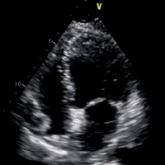

Bedside Cardiac Ultrasound to Aid in Diagnosing Takotsubo Cardiomyopathy

A case of a 64-year-old patient presenting with new-onset chest pain and shortness of breath illustrates the utility of bedside cardiac ultrasound...